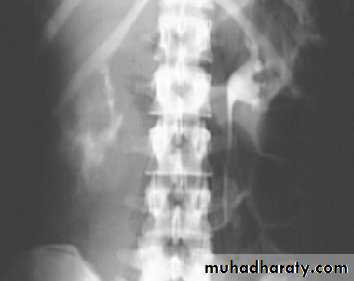

Horse shoe kidney :-*lower poles fused *low positioned kidneys *parallel to spines.*malrotated medially